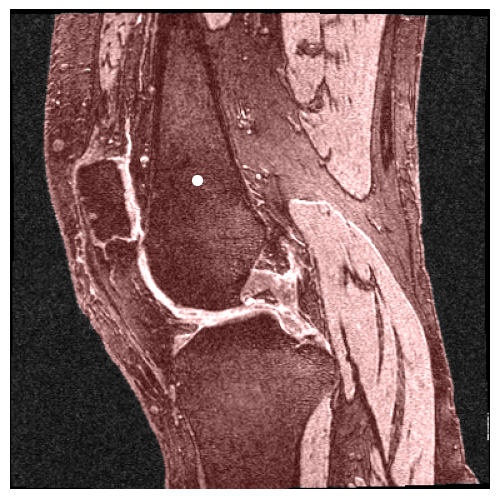

In our work, we extend SAM2 to 3D MRI images by treating slices from 3D volumes as individual video frames. As shown in Figure 1, this method leverages SAM2’s video segmentation capabilities to process 3D data efficiently, enabling precise segmentation of volumetric medical images with minimal user input. This extension significantly enhances SAM2’s performance in medical imaging tasks, achieving higher accuracy and efficiency. Specifically, for zero-shot single-prompt segmentation of knee MRI images, SAM2 achieves accurate results with minimal interaction, thus improving the overall workflow of medical image analysis.

Knee MR volumes from the Osteoarthritis Initiative (OAI) were collected, alongside segmentations of the femur and tibia provided by Zuse Institute Berlin (ZIB). The 488 volumes, each with a matrix size of , were acquired using the 3D double-echo steady state (DESS) sequence, automatically segmented combining statistical shape modeling, then manually corrected to produce the OAI-ZIB dataset[8]. The corrected bone masks were used as ground truth targets in this study.

This study focused on the usage of point prompts to direct SAM1 and SAM2’s predictions. Using the ground truth masks of the femur and tibia, the center of each bone’s mass was computed for each slice of the volume. The density of the bone was assumed to be uniform throughout the slice, and thus the computed center of mass was equivalent to the centroid. In addition to the centroids, one more point prompt per volume was manually generated, pointing to the patella on the middle (80th) slice. With two point prompts per slice and 160 slices per volume, plus one prompt for the patella, a total of 321 point prompts were generated for each volume. This study also used bounding boxes, generated using the same ground truth bone masks. The min and max and values of each bone mask in each slice were used to delineate the square region containing the bone. With four points per box, two boxes per slice, and 160 slices per volume, a total of 1280 points were generated for each volume.